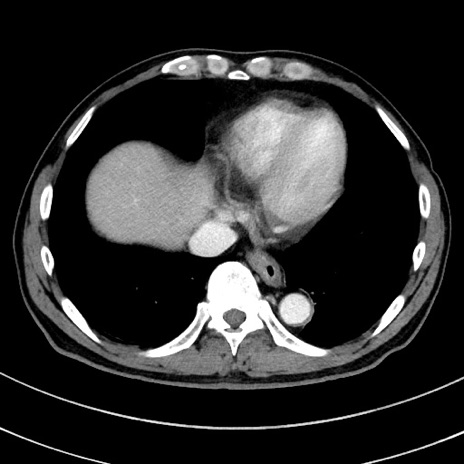

冠状断像